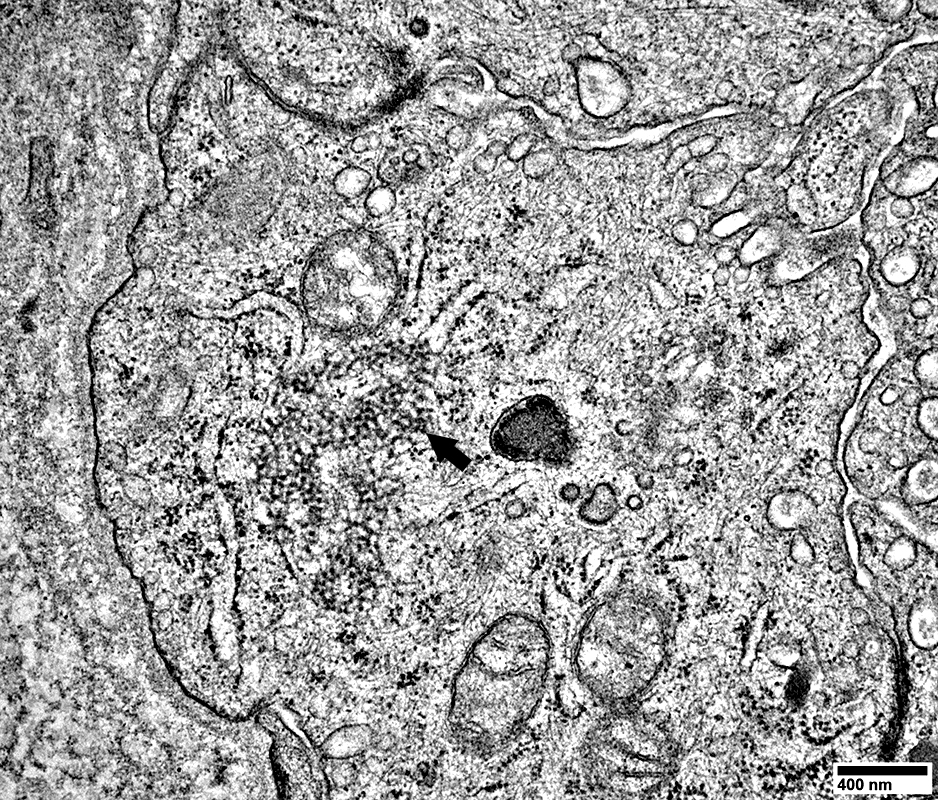

From R Schmidt

Endomysial capillaries

Size: Large

Endothelial cells

May contain tubuloreticular profiles (Below; Arrow)